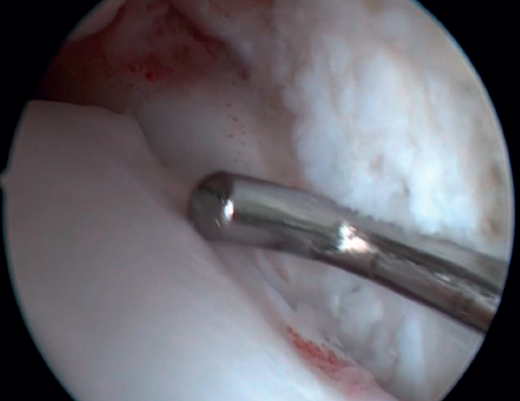

Resection of the osteophyte is performed by displacing from the top, and gradually reducing it until the joint zone is reached (Figure 2). A basket forceps can be used to resect the area closest to the joint (Figure 5). It is often useful to exchange the viewing and working portals in order to visualize and completely resect the osteophytes. In the case of soft tissue impingement, a 3.8 or 4 mm synoviotome is usually sufficient. The vaporizer is useful in the case of compact impingements, typical of post-traumatic conditions or re-interventions, and also for delimiting the bony part of the osteophyte before resection.

Figure 5. Resection of the part closest to the talar cartilage can be completed with a basket forceps to minimize damage to the joint cartilage.